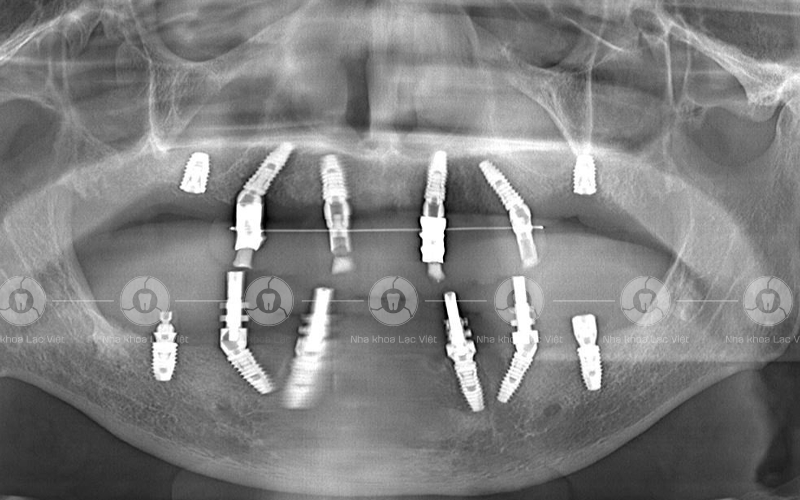

Sau khi thăm khám kết hợp chụp CT Conebeam, Scan trong miệng, các bác sĩ đã đưa ra kế hoạch điều trị cho anh Thường:

• Cắm 4 trụ Implant hàm trên và 4 trụ Implant hàm dưới

• Phục hồi 12 răng mỗi hàm

• Khôi phục 95% chức năng ăn nhai

Hình ảnh phim chụp sau cấy ghép implant của anh Thường (Ảnh: Nha khoa Lạc Việt)